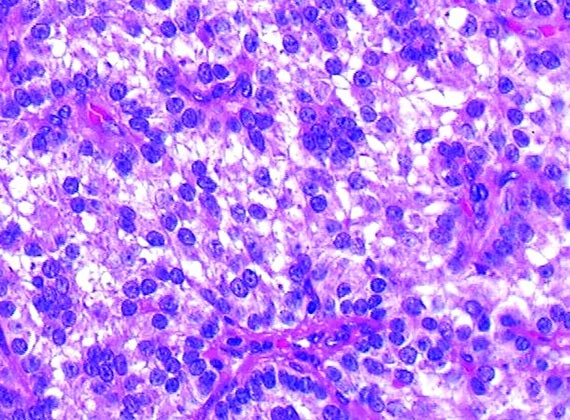

FIGURE 3

Carcinoma with neuroendocrine features. Note rosettes and peripheral arrangement of nuclei with eosinophilic granular cytoplasm and finely granular chromatin (lung FS, H 40 × ;TIF).